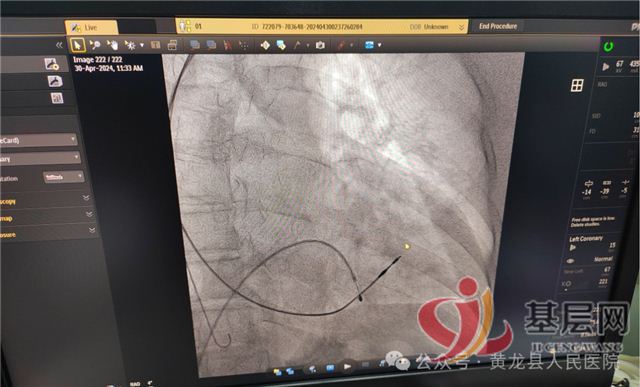

收住入院,完善相关检查,明确诊断后将患者病情及手术治疗等情况告知家属,家属有意愿在县医院手术。内科主任吕宏伟将情况积极向院领导汇报,医院积极安排唐都医院心内科帮扶专家纪兆乐和我院重症监护室主任、内科副主任王永斌为患者手术。专家详细查看患者,积极完善术前准备,征得家属同意后于“五一”节前最后一天,在介入手术室顺利完成心脏双腔永久性起搏器植入术,术中患者没有任何痛苦,术后起搏器工作正常,患者自我感觉良好以往的不适症状也得到了缓解。

患者术前心电图检查

患者术后心电图检查